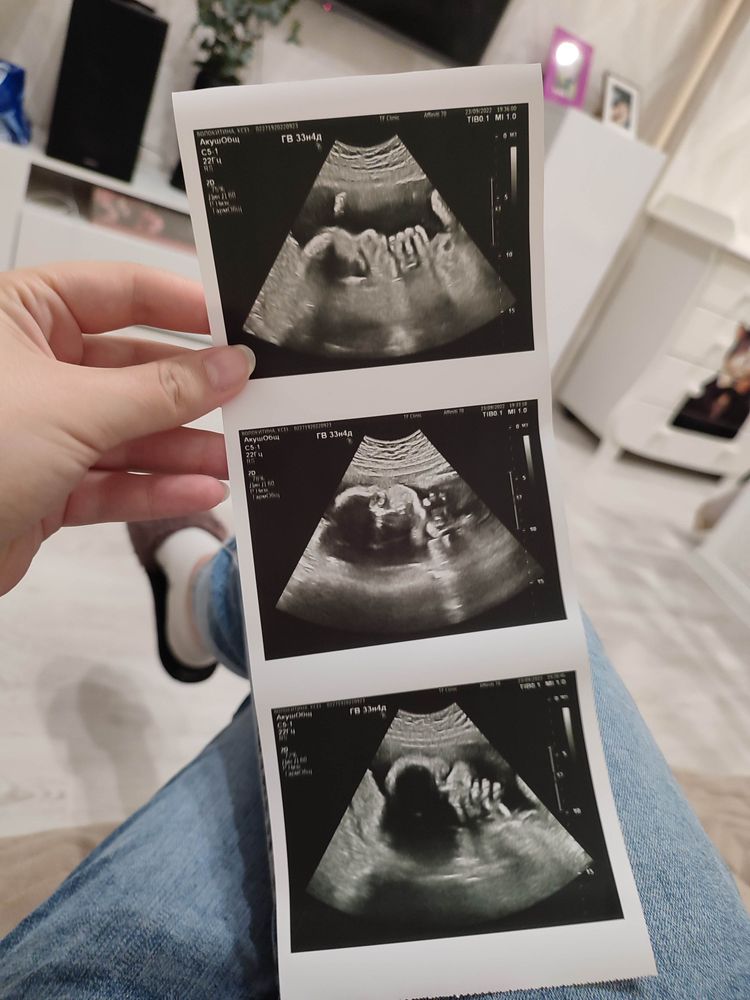

34 недели🌺🤰Малыш сидит на попе.

Время быстро полетело. Расслабляюсь и занимаюсь покупками.Набрала 11 кг,перестала держать диету😀чувствую себя довольно активной, только кости или связки на лобке побаливают. И самое главное были сегодня на УЗИ, всё хорошо малыш весит 2300, размеры соответствуют сроку, только расположение не правильное. Девушки, у кого было так же? Переворачивались ли ваши пупсы к родам? Если да, то что помогло? Если нет, то как родоразрешали?

Аналогично. 33+4

с 30 недель сел на попу.. и вот пока что так и сидит